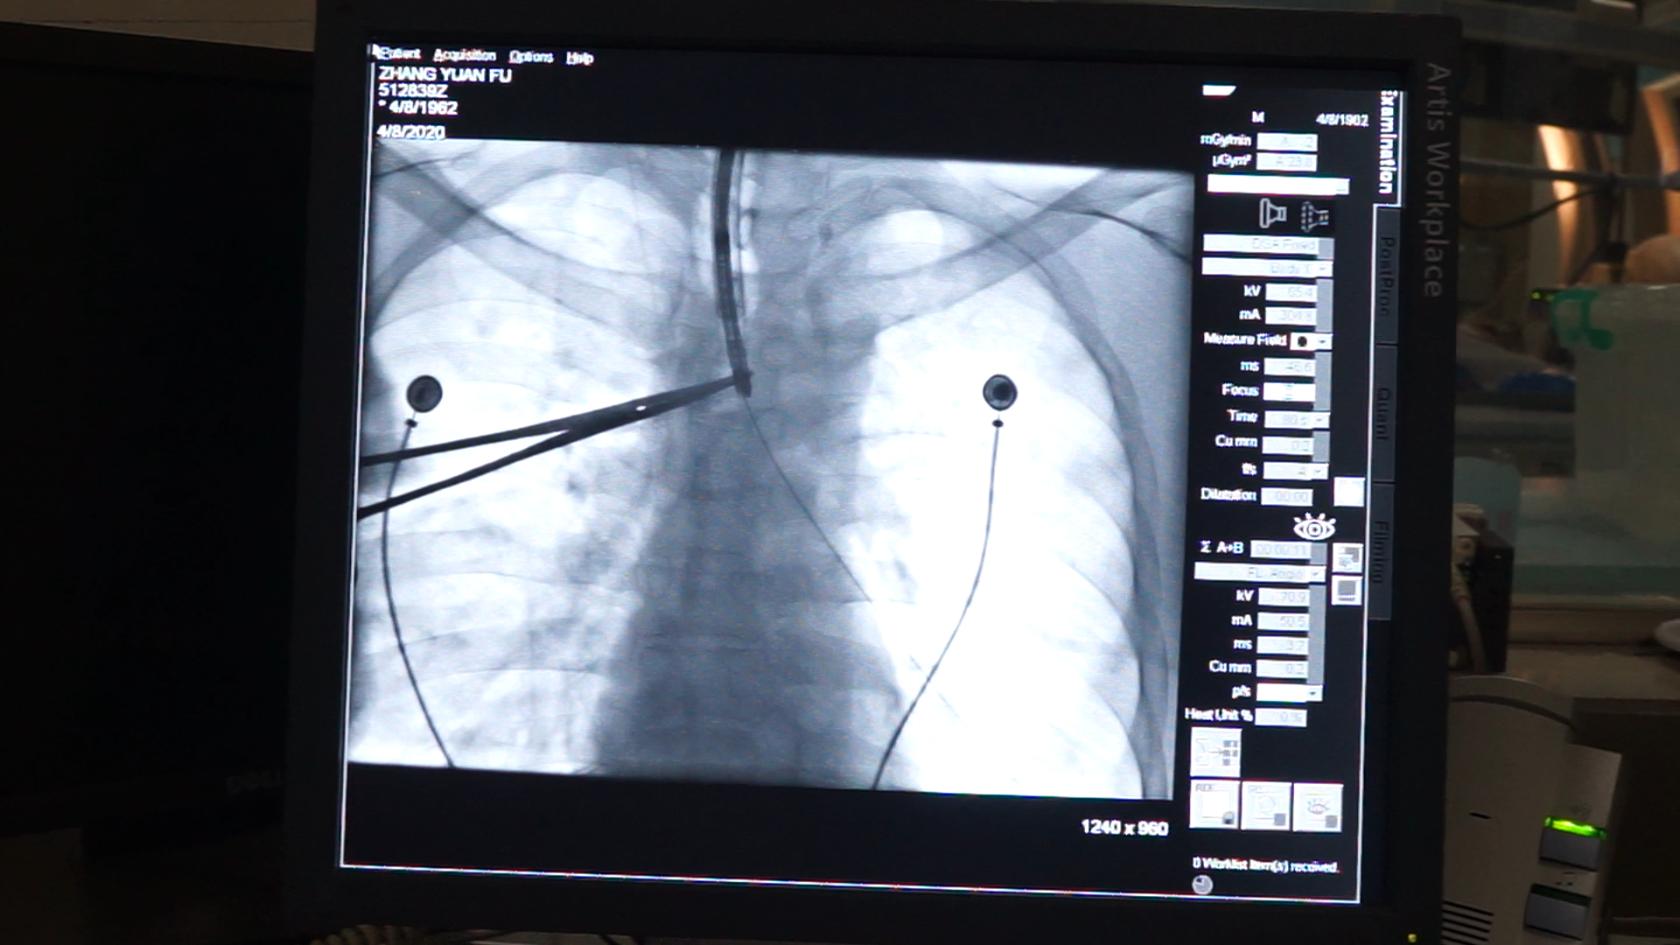

入院完善相关检查发现患者的纵隔、心脏、气管向左侧移位;右侧支气管及部分分支管腔变窄、狭长,内壁欠光滑。右肺可见多个小结节状高密度影,较大者位于右肺上叶前段,大小约1.7x1.2cm,边界模糊不清。纵隔内可见稍大及小淋巴结,较大者位于隆突下,大小约1.2x0.8cm。由于患者气道狭窄严重呼吸困难,医院专家立即综合评估病情,并在患者及家属的同意下,施行右支气管射频消融术+DSA定位下右支气管支架置入术,可及时开通阻塞气道,引流分泌物,改善患者临床症状,同时热消融使肿瘤周围的血管组织凝固,从而减少或阻断肿瘤血供,防治肿瘤扩散,为下一步治疗赢得时间。术后,患者胸闷、气喘症状明显改善。